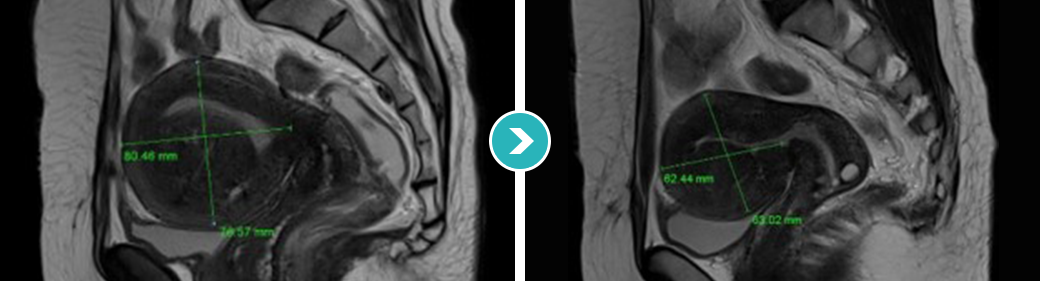

심한 생리통과 항문통증으로 자궁선근증이 진단되어 자궁선근증 하이푸 치료를 위해 입원하셨습니다.

하이푸 시술전 MRI사진상 자궁은 6.5크기로 커져서 자궁후벽을 중심으로 자궁선근증성 변화가 관찰됩니다.

아래의 MRI 사진은 자궁선근증 하이푸 시술 전후의 사진을 비교한 사진입니다. 자궁선근증 하이푸 치료후 90%이상 치료되어 치료부위가 회색과 검은색으로

나타나며, 차후에 좋은 경과를 기대하며 가장자리의 잔여병변은 호르몬 치료하면서 경과관찰 하시도록 하였습니다.